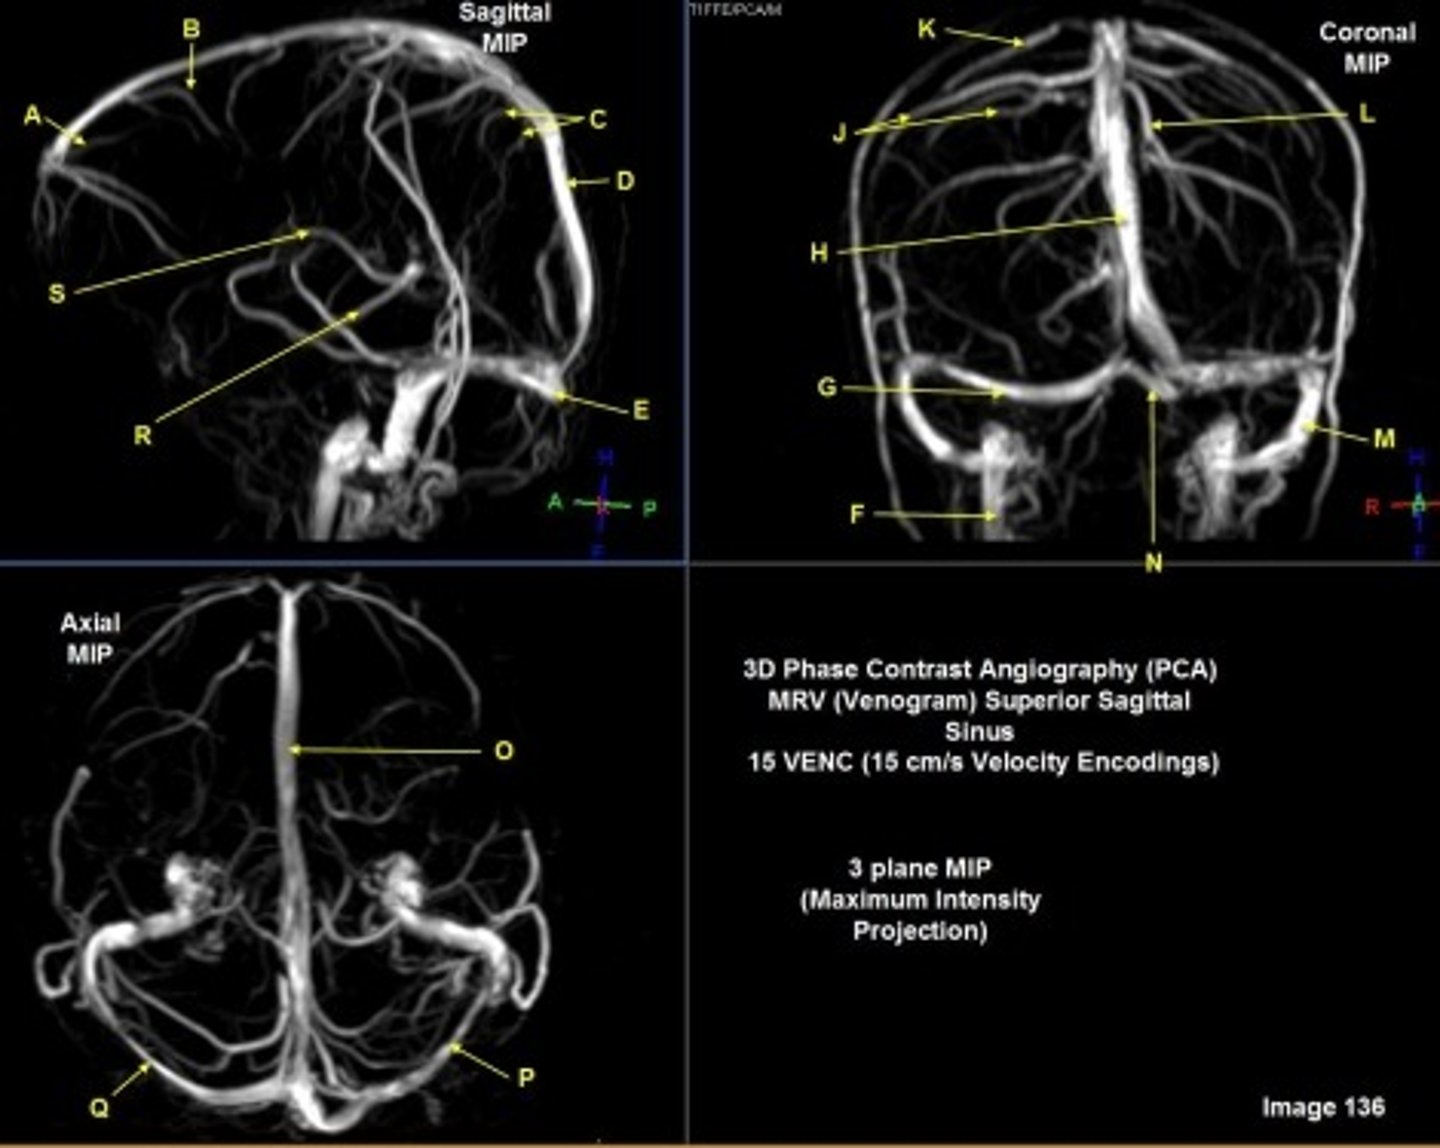

what kind of image is this?

MRA extracranial circulation

A, where does it supply blood to?

external carotid artery

face

B, where does it supply blood to?

internal carotid artery, anterior brain

C

Common carotid bifurcation

D

common carotid artery

E, where does it supply blood to?

vertebral artery, posterior brain